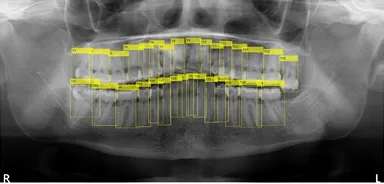

歯牙の全自動認識法

従来、歯科医院ではパノラマレントゲンの撮影後、歯科医師が目視で患者の歯牙情報をカルテや患者管理ソフトに入力し、診査・診断等を行っていました。本システムは、パノラマレントゲンの画像データから歯牙情報の有無をAI技術で自動解析し、また解析後の歯牙情報をアウトプットするものです。